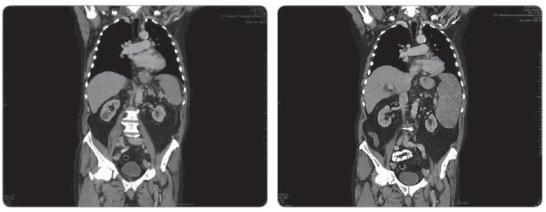

V roce 2010 navštívil naši kliniku 73letý muž s anamnézou 2 roky trvajících obtíží a tlaku při zbytnění levého podpaží. Nález jsme indikovali k histologickému vyšetření se závěrem vs primárního nízce diferencovaného kožního apokrinního adenokarcinomu. V rámci vstupních stagingových vyšetření podstoupil PET/CT, které potvrdilo dvě aktivní uzliny v levé axille. Ultrazvukové vyšetření prsních žláz vyloučilo primární malignitu v oblasti mamm, panel tumor-markerů byl negativní. Pacient byl indikován k exenteraci levé axilly, při které bylo odstraněno 5 uzlin, ve dvou byla nalezena metastáza karcinomu se žlázovou diferenciací, resekční okraje byly volné. Následně pacient podstoupil ozáření axilly do celkové dávky 44 Gy a dále byl sledován. V srpnu 2011, tedy 10 měsíců po ukončení primární léčby, jsme zaznamenali vzestup tumor-markeru CYFRA 21-1. Na kontrolním PET/CT vyšetření byla nalezena recidiva nemoci s metastatickým postižením skeletu, v březnu 2012 se přidalo i postižení sleziny. Biopsie kostního procesu potvrdila původ v apokrinním karcinomu. Následně byl pacient indikován k systémové léčbě (CBDCA + paklitaxel), při které ale nemoc rychle postupovala na další orgány (játra, kůže hrudníku, viz obr. 1, 2). Původní histologický materiál i excidované kožní ložisko jsme podrobili histologické expertíze, při které byl stanoven také stav hormonálních receptorů a nalezena 100% exprese androgenních receptorů. Na základě výsledku jsme v říjnu 2012 zahájili terapii bicalutamidem, kterou pacient velmi dobře toleroval a při které bylo dosaženo parciální odpovědi v oblasti sleziny (obr. 3) a kůže, nicméně v ostatních lokalitách došlo k progresi nemoci a nově se objevila retroperitoneální, mediastinální a hilová lymfadenopatie. Toho času je pacient ve velmi dobrém výkonnostním stavu a jeho kvalita života je přes rozsáhlý nález generalizace základní nemoci také velmi dobrá.